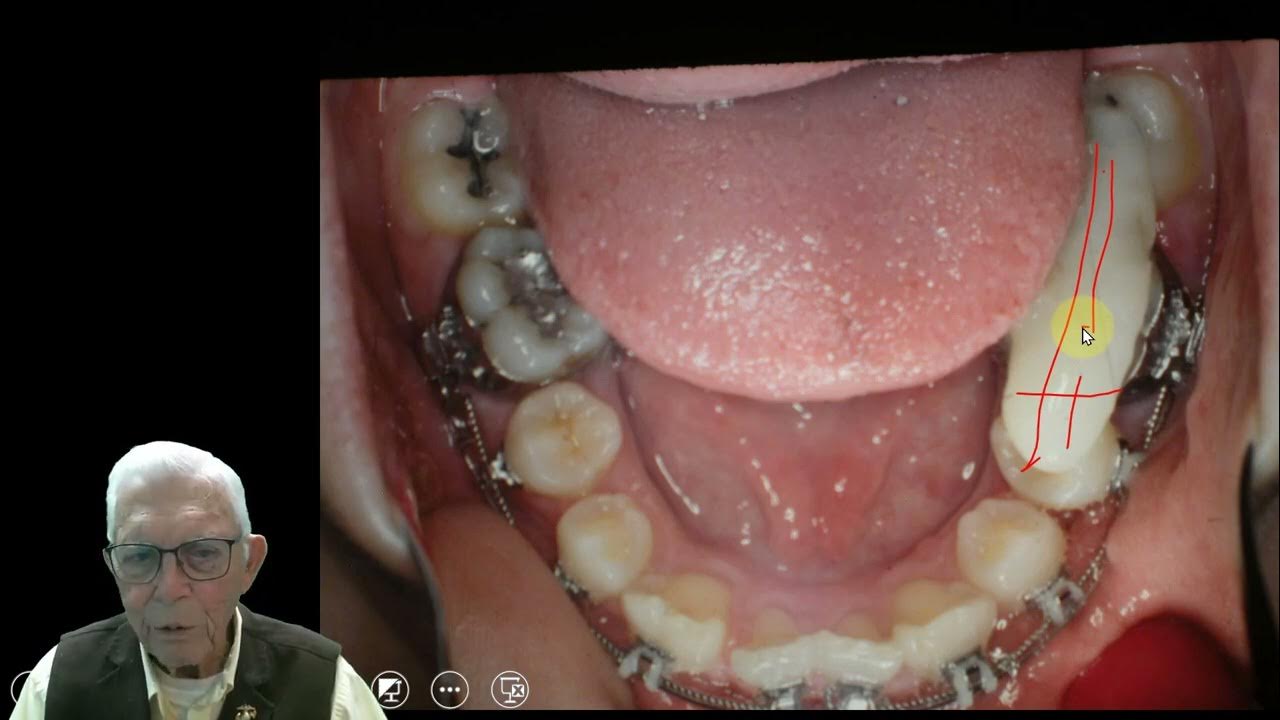

From www.youtube.com

2. I Got Braces Today! PICS + Eating, Bite Block, & Pain YouTube Bite Blocks Causing Pain This is because you are chewing in. A bite block helps you during braces treatment by preventing breakage of the brackets or popping them off when you bite. It is usually made of soft material and fits comfortably over the teeth. Braces can cause temporary pain, and adding bite blocks may intensify over the short term. Although bite turbos can. Bite Blocks Causing Pain.